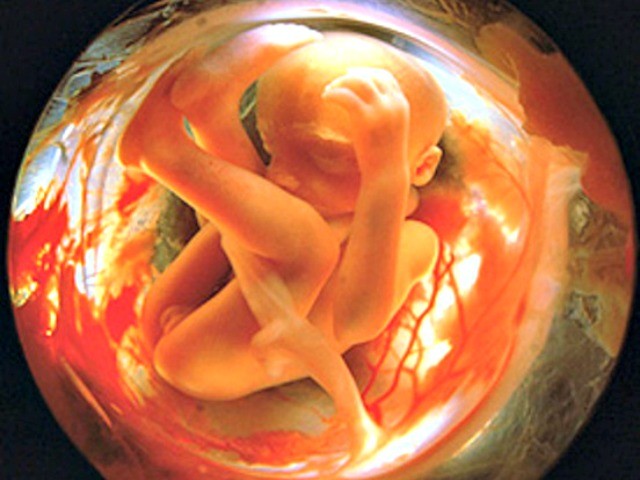

16-17 недель беременности: развитие малыша

Раздел: Житейские мотивы